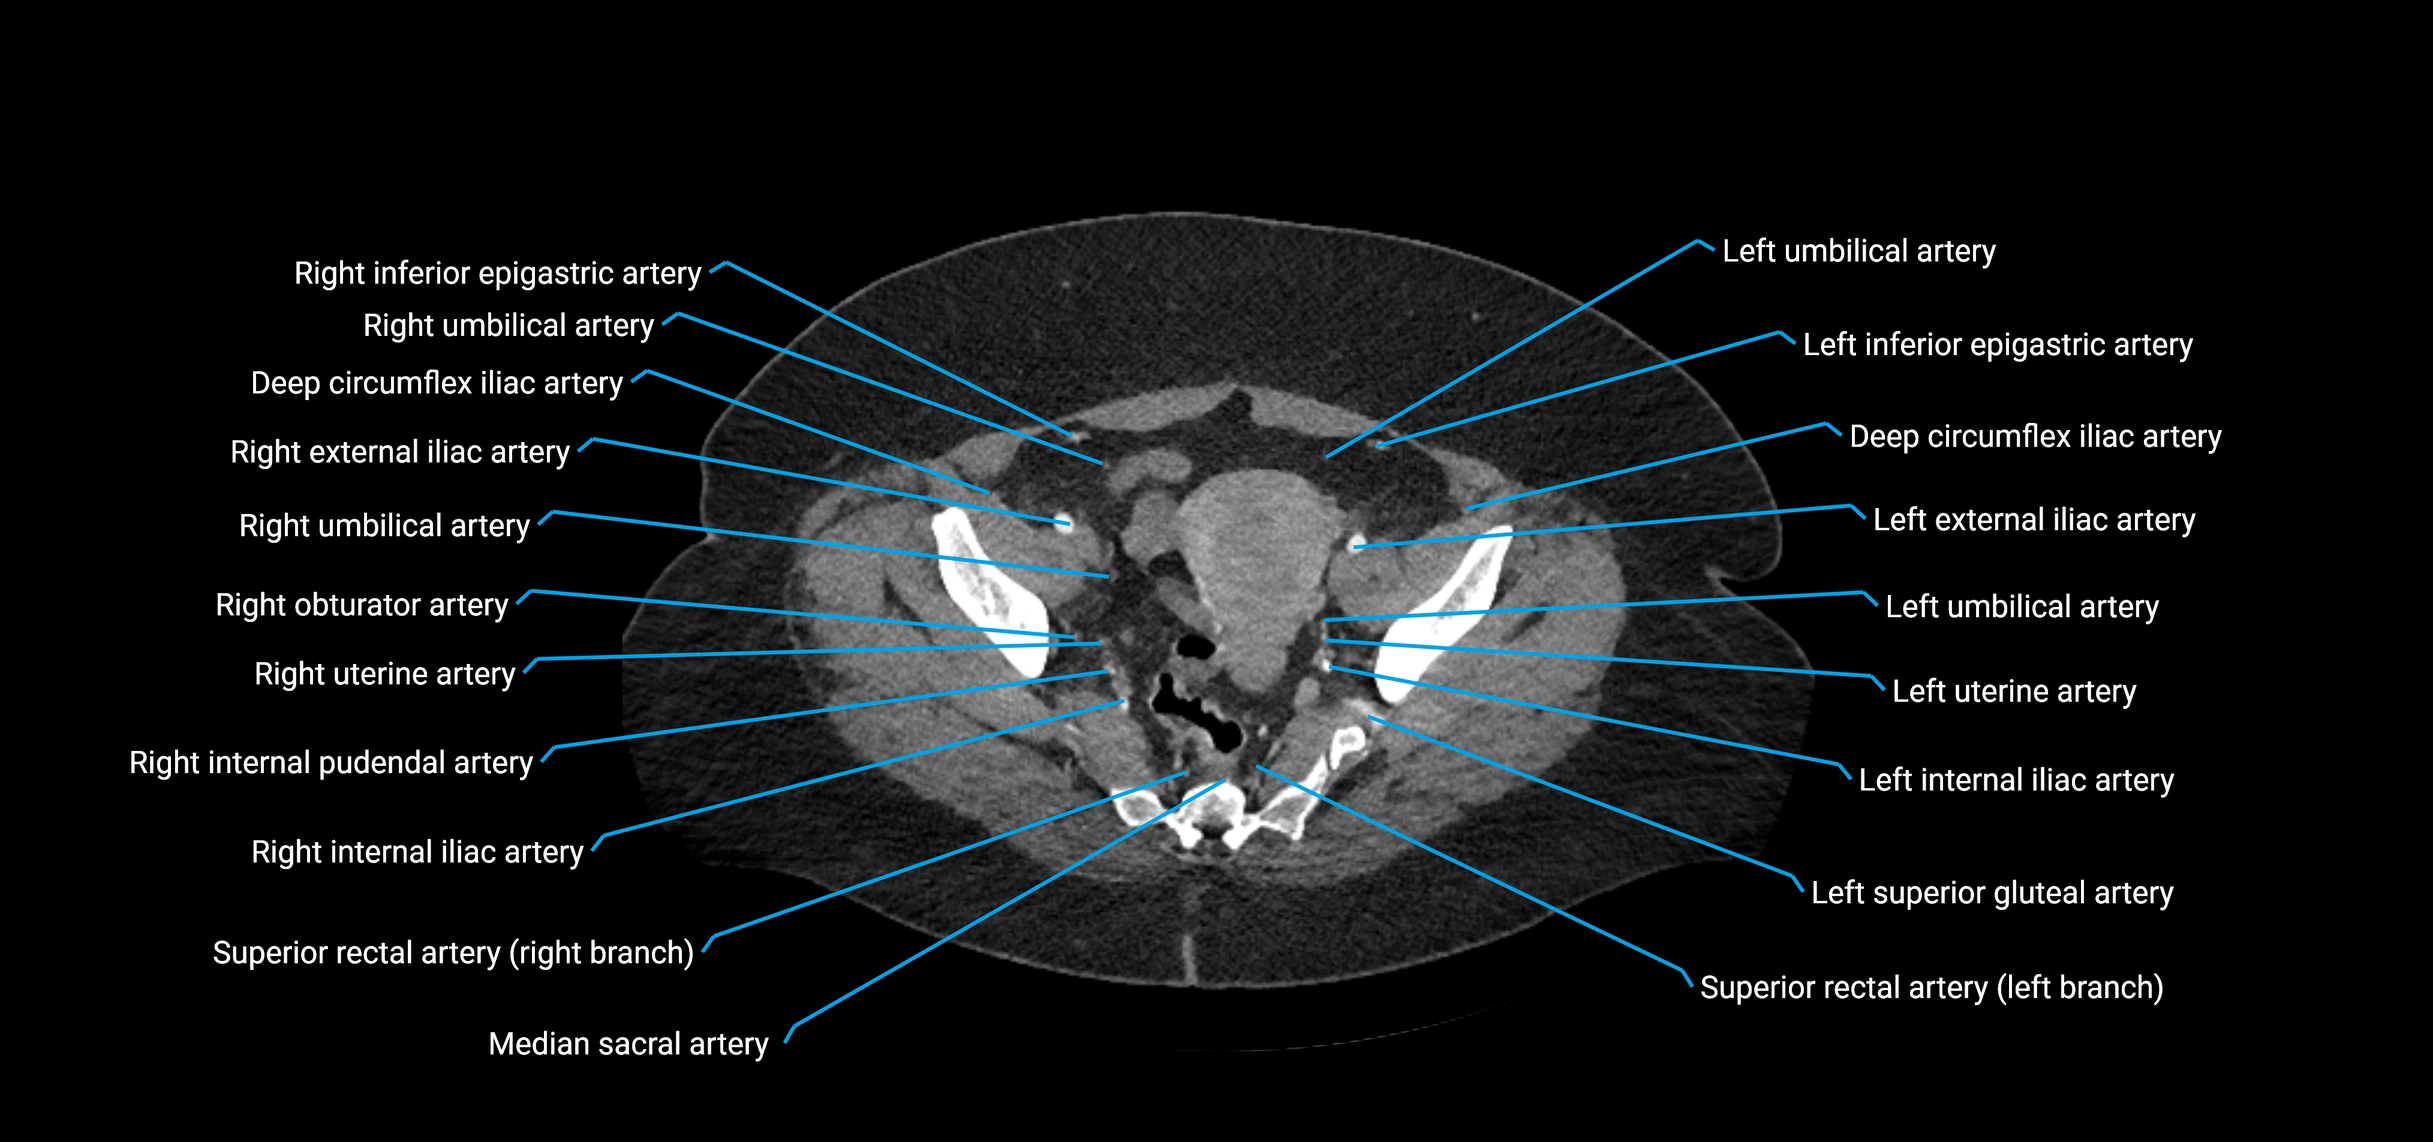

CT images

image

Contrast-enhanced CT (CTA):

• Gold standard for abdominal aortic imaging

• Provides excellent detail of lumen, wall, aneurysm, thrombus, and branch vessels

• Multiplanar and 3D reconstructions help in aneurysm measurement, stent graft planning, and dissection evaluation